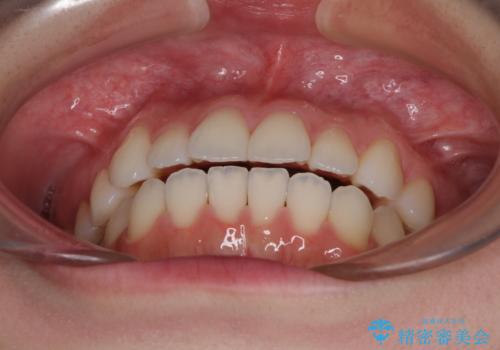

後戻りは軽微でしたが、舌突出癖が認められ、初診時には上下前歯に舌がはまるスペースができていました。

舌突出癖の改善により上下前歯が接触するようになり、前歯でものを咬みきる必要のある食事がスムーズに行えるようになりました。